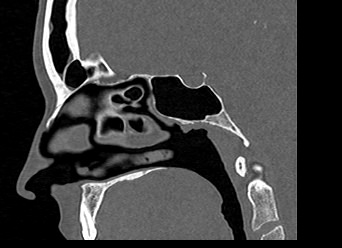

В современной отоларингологии широко применяется мультиспиральная компьютерная томография для диагностики различных заболеваний ЛОР-органов. КТ относится к лучевым методам исследования, который с помощью рентгеновских лучей позволяет получить детальное изображение костных структур, хрящей носа, околоносовых воздухоносных пазух и прилегающих областей.

Воспалительные заболевания, такие как гайморит или синусит верхнечелюстных пазух, этмоидит, сфеноидит и фронтит достоверно визуализируются при помощи компьютерной томографии. Полученные данные помогают врачу специалисту в верификации диагноза и утверждении эффективного плана лечения. На фоне воспалительных изменений нередко встречаются полипозные образования, а при запущенных случаях синуситов очень важно подтвердить или исключить наличие участков деструкции костных перегородок.

Преимуществом КТ является ее способность отлично визуализировать кости лицевого черепа, что делает методику незаменимой для оценки любых травматических повреждений носа, выявления аномалий развития носовой перегородки и, деформации хрящей.

Аппараты сканируют область исследования в течение нескольких секунд, производя одномоментно от 64 до 128 тончайших срезов толщиной от 0,5 мм. Высокая скорость сканирования обеспечивает минимальную дозу облучения для пациента. При этом получаются четкие изображения с высоким контрастным разрешением, что дает возможность рассмотреть исследуемую зону в мельчайших подробностях. Кроме того, томографы создают объемные 3D-изображения области носа и прилегающих пазух, что помогает в оценке пространственного соотношения анатомических структур, выявленной патологии и способствует проведению точной диагностики.

Что показывает КТ носа

- полипы;

- опухоль (злокачественная и доброкачественная);

- инородные тела в указанной области;

- воспалительный процесс (утолщение слизистой оболочки, жидкость, признаки гноя);

- повреждение костей.